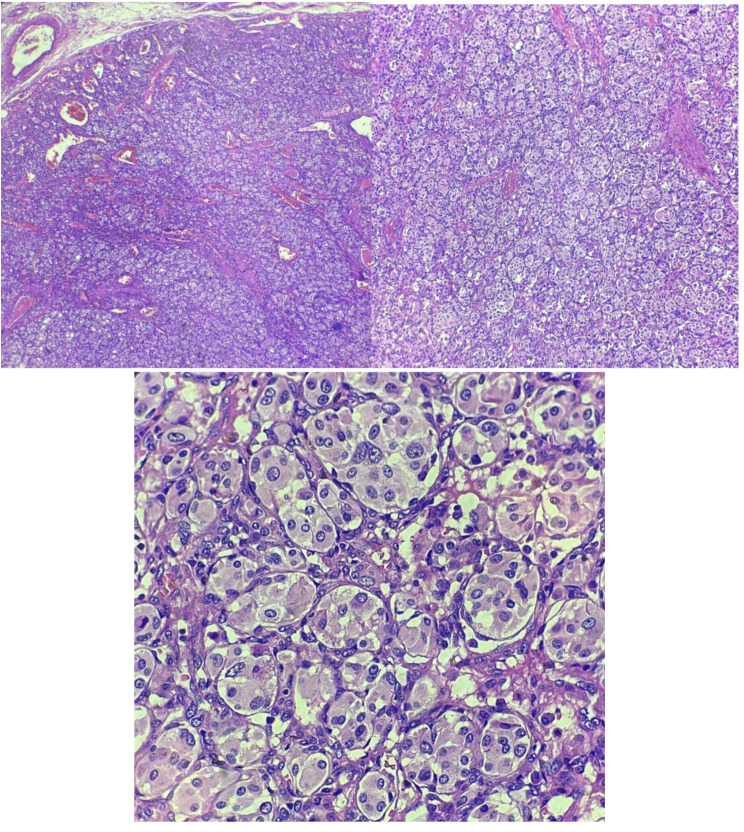

Case presentation: The patient was a 46-year-old male with a history of surgical removal of a mass from the right side of the neck, who presented with dysphonia lasting two months, hoarseness, vague chest pain, and unilateral ptosis. CT angiography of the carotid arteries and thoracic aorta revealed multiple findings, including a well-defined enhancing mass measuring 33 × 39 mm in the aorto-pulmonary prevascular space, a grade I carotid body tumor on the left side of the neck, vagal paragangliomas on the right side of the neck, and a glomus jugulare tumor on the right side. These findings were collectively suggestive of multiple paragangliomas. The patient subsequently underwent surgical resection of the mediastinal tumor, and pathological examination confirmed the diagnosis of paraganglioma.